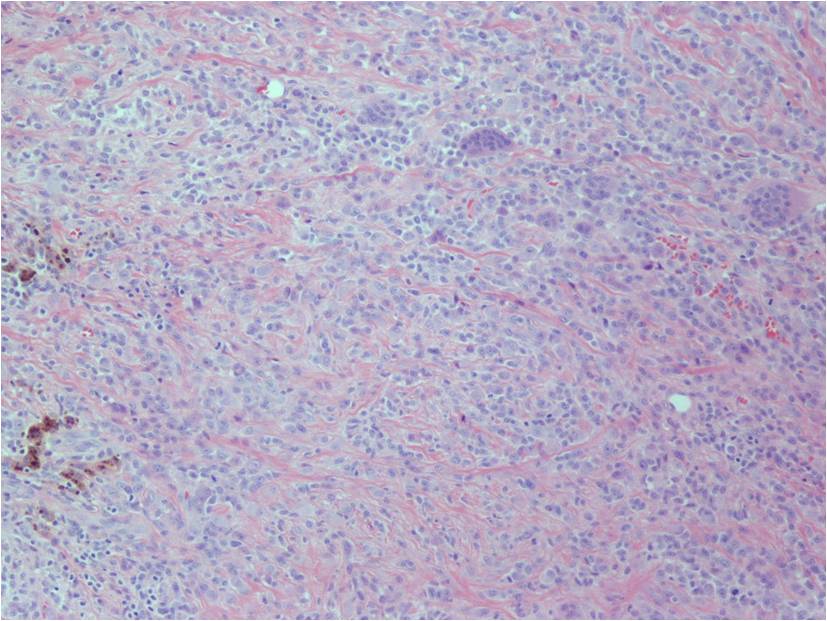

Microscopic (Fig. 12-14)

- Highly cellular

- Lipid Laden Macrophages

- Small polygonal

- Scant cytoplasm

- Spindled cells (with pale cytoplasm)

- Xanthoma cells

- Multinucleated giant cells

- Prominent chronic inflammatory cells

- Foams cells are observed in the periphery of the lesions.

- Hemosiderin pigment prominent

- Stromal and fibroblast cell proliferation

- Numerous cleft-like (alveolar) spaces

- Variable degree of villous, nodular and pigmentation (hemosiderin) and inflammatory components

- Frondlike synovial projections

Fig. 12-14: Highly cellular sheet of spindled cells, multinucleated giant cells and chronic inflammatory cells with variable degree of pigmentation (hemosiderin). Numerous cleft-like spaces or ‘pseudoglandular’ spaces, surrounded by xanthoma cells. Cleft-like spaces are commonly seen in diffuse-type giant cell tumors.